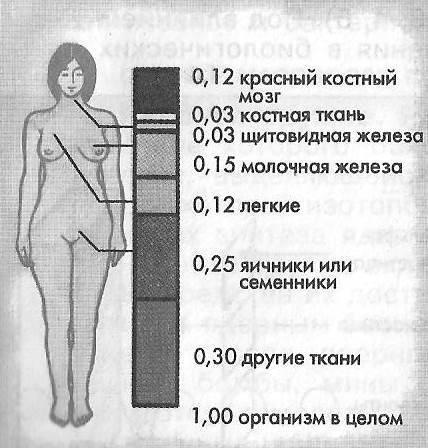

Изучение дозы излучения при рентгеновских исследованиях: визуализация